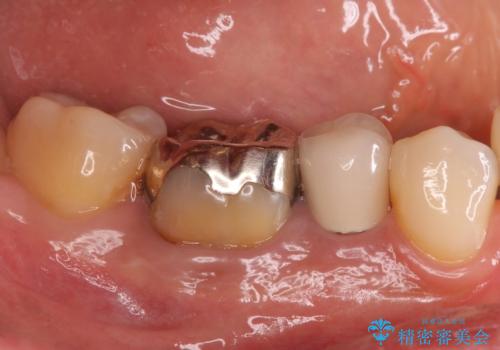

目立つ銀歯を白くしたい ジルコニアクラウンでの修復

- 口を開けたときに下の歯の銀歯が目立つから白くしたいとのことで来院されました。

根管治療はご希望されなかったため、被せ物のみをやり替えていきます。

- 右下6 仮歯+ジルコニアクラウン 11,000円+121,000円費用は治療当時の料金となります